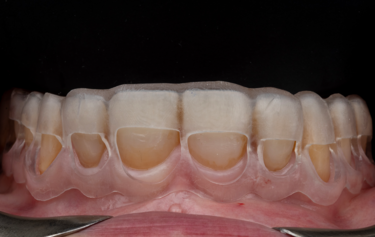

Figure 15: Actual-size and over-sized 3D printed working models

On receiving the scans of the final tooth preparations, the laboratory was able to overlay the planned final restorations which the milled temporaries had been based upon. The small modifications to the occlusion which was completed at the earlier temporary stage could be adapted into the digital design, and then the individual restorations adapted to the refined finishing margins of the final tooth preparations (Fig. 14). The final restorations were then milled in IPS e.max ZirCAD Prime Esthetic in the lighter BL4 shade using the PrograMill PM7 milling unit. New working models were 3D-printed of the preparations, and a second set of oversized models were made to compensate for the increased size of the pre-sintered Zirconia (Fig.15). The larger model was scaled up to match the shrinkage factor of the zirconia to allow the restorations to be checked on the oversized model. This additional check stage allows for assessment of marginal fit and contact areas, in addition to checking the passivity of fit and the occlusion, ahead of sintering.

Some subtle surface shade modifications were then completed using a pre-sintering infiltration technique and IPS e.max zirconia colouring liquids (Fig. 16). Some B1 dentine shade was used in the cervical third to increase the chroma, and some blue and grey was used towards the incisal third to increase the appearance of translucency. A little orange shade was also used in the occlusal area of the posterior teeth. The restorations were dried in line with manufacturer recommendations, and they were then sintered in the Ivoclar S1 1600 furnace. After sintering the crowns were checked on the regular-sized working model, and because all these checks had already been made pre-sintering then there were no adjustments necessary. Additional surface texture was added and then the restorations were polished using rubber polishers. Some final characterisation was added using IPS Ivocolor and glazed with IPS Glaze Fluorescence. The final restorations have the perfect balance of individual character and depth of colour to mask the underlying tooth preparation, as well as the graduation of translucency to replicate that of natural teeth (Fig. 17).